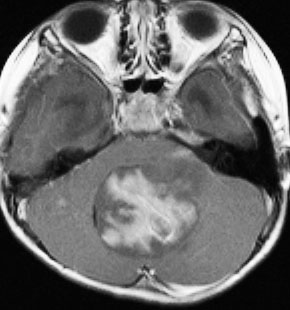

髄芽腫治療後17年目,放射線誘発血管腫からの脳幹部出血

1歳5ヶ月で左小脳半球の髄芽腫になり手術と化学療法して,3歳になってから脳脊髄照射をしました。脳脊髄18グレイ,局所48グレイが入っています。18歳の学生の時のMRIで,左小脳萎縮がありますが普通の生活ができています。

18歳の時に突然,左上下肢の痺れと脱力が生じました。延髄下端から脊髄に小さな出血があります。様子を見ていたら症状はよくなりました。

その後数日の間に,小さな出血を繰り返して,嚥下障害,しゃっくり,頭痛,四肢のしびれなどが出ました。手術をしないで経過を見ました。

7年後のMRIです。延髄脊髄移行部(おそらくC1)に出血痕が残っています。放射線誘発海綿状血管腫といわれるものの画像所見ですが,ほんとのところは静脈閉塞によるうっ血症状と鬱血性の出血といわれています。

症状はすべて良くなりました。今は学校を卒業して,元気に働いています。